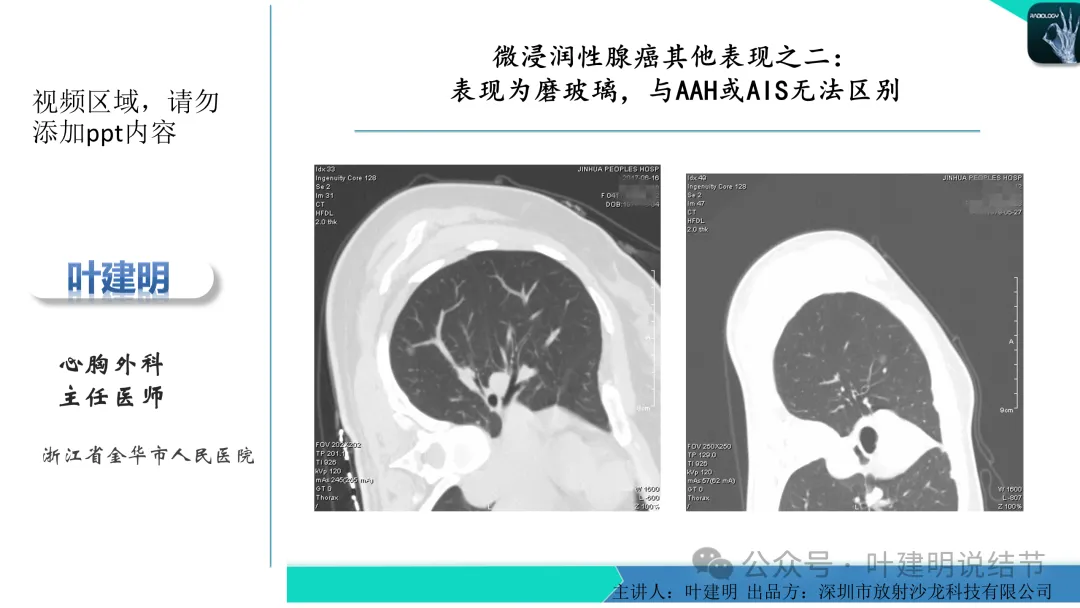

右上叶淡磨玻璃结节,才3-4毫米许,还很小,而且密度非常低,不过轮廓较清,边缘无膨胀性,像肺泡上皮增生。

左下叶结节,轮廓稍显模糊,邻近有血管走行,无血管弯征,病灶中间密度稍低,结节密度很淡,仅小片状模糊影似的。

当地说考虑微浸润性腺癌的左下主病灶影像连续层面展示:

病灶出现,显模糊。

上图层面轮廓较清,但密度很淡,似见血管走行,但靠左前方的似条状磨玻璃密度与血管连着的到底是血管分支还是结节的一部分,其实并不确切。如果其实是血管分支,那病灶与它之间就不是空泡。

病灶在此层整体边缘显糊,灶内有空泡似的,瘤肺边界欠清。

边缘不平,还是灶内多发小空泡?邻近血管与之紧贴,但血管无异常走行。病灶密度很低,显糊。

中间所谓空泡更像是细支气管扩张,内壁非常光滑且圆形。

病灶边缘区淡而模糊。

这个病灶会是微浸润性腺癌吗?当然没有病理诊断,我也不能说百分之百必不会,但这样的病灶已经风险大到必得尽快手术切除干预了吗?显然还早着呢:1、影像不是典型的结节状;2、边缘与轮廓模糊不清;3、灶内似有细支气管扩张(更容易是细支气管扩张伴少许周围炎或肺泡上皮增生);4、血管邻近走但无牵拉影响;5、没有实性成分,没有锐利毛刺,没有胸膜牵拉,没有血管进入,没有任何倾向风险性高的影像特点。我一直强调:肺结节是否要干预处理,不要纠结于最后病理是什么,而要看风险高低;而风险高低的最重要术前判断依据一是随访有无进展,二是有没有实性成分。只要没有肉眼可见的影像上的实性成分,风险就是低的!何况病理也是人看的,原位还是微浸润,不典型增生还是原位有时也在一念之间。